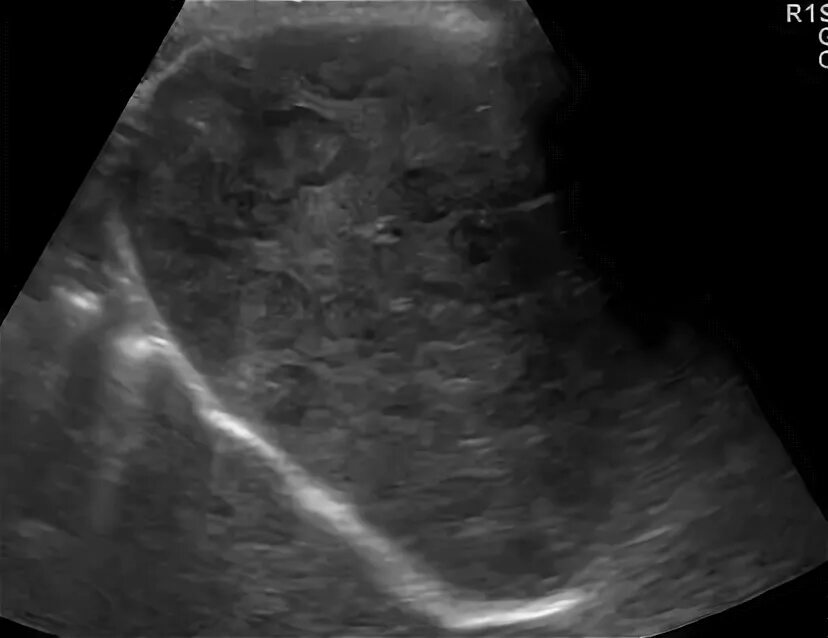

Метастазы в печени на узи